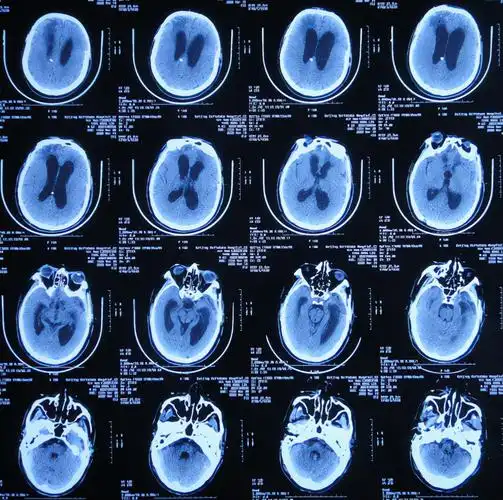

值班必备 | 急诊颅脑ct常见的八种疾病

头颅ct解剖与常见出血梗死判读

读片训练丨10例颅脑正常变异与先天异常的ct图像